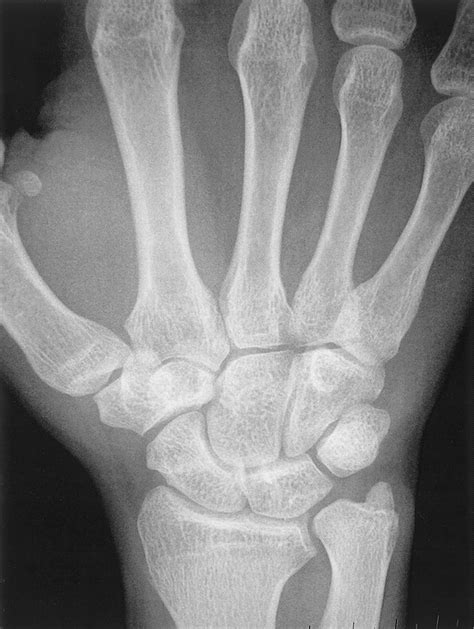

To understand Positive Ulnar Variance, one must first visualize the anatomy of the forearm. The forearm consists of two parallel bones: the radius (on the thumb side) and the ulna (on the pinky side). In a neutral wrist, these bones are relatively even at the wrist joint. When an individual has positive ulnar variance, the ulna extends further toward the hand than the radius does.

This structural discrepancy means that the ulna bears a disproportionately large amount of force when you use your wrist, particularly during gripping, twisting, or weight-bearing activities. Over time, this chronic over-loading can lead to wear and tear of the structures nestled between the ulna and the small bones of the wrist, known as the carpal bones.